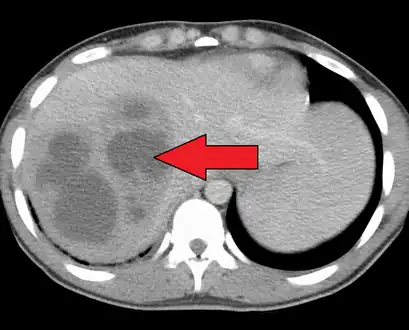

- USG and CT scanning